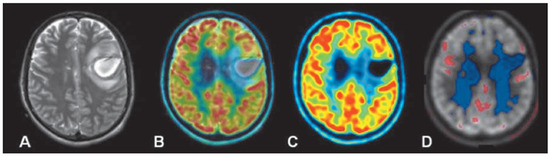

Neurobehavioural evaluation of disorders of consciousness

by Jane Jöhr, Jean-Michel Pignat and Karin Diserens

Although diagnostic guidelines for disorders of consciousness (DOC) have been consensually defined and are broadly used worldwide, a very high rate of diagnostic error remains among patients with DOC. Such failure to discern accurately between the different states of altered consciousness may influence tremendously the accuracy of prognosis, the decision-making process and medical care management or withdrawal. As there is no direct way to detect consciousness, one needs to infer its presence from behavioural observations and clinical examination at the bedside. Guidelines informing how one should approach clinical assessment of DOC have not yet reached the gold standard of diagnostic methodology. In the context of increasing demand for acute neurorehabilitation in Switzerland, there is a crucial need to improve the accuracy of initial diagnosis and prognosis, which profoundly impact treatment decisions in the short and long term. Validated neurobehavioural scales commonly used in our acute care setting are reviewed and their limitations considered. We assume that underlying deficits such as a severely damaged motor system compromise the detection of consciousness in the acute stage. Bearing out this claim, the results from our longitudinal pilot study demonstrate that the additional use of a new set of clinical items specifically oriented towards the observation of subtle aspects of motor behaviour in the acute phase helps to identify better the signs of consciousness with a strong predictive rate. According to our findings, many patients are potentially misdiagnosed with severe impairment of consciousness when rated with existing scales, whereas their condition prevents them from succeeding in the production of an adequate motor or verbal response. Such complex and alarming situations call for future profound modifications in DOC assessment. We posit that the development of a coordinated multimodal approach combining information from different sources will help in reaching an objective appreciation of DOC, overcome the current behavioural-based misdiagnosis issue and, most importantly, improve the care of DOC patients in the acute phase. Full article